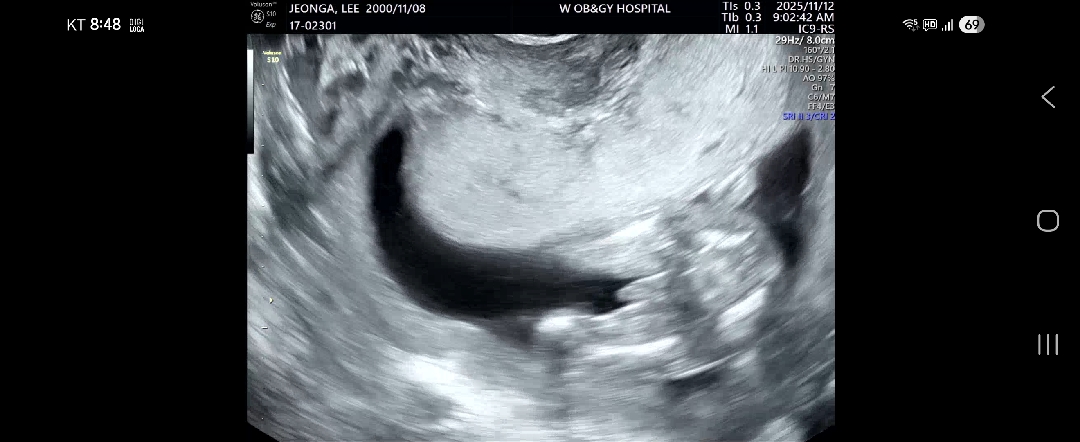

이때까지아기가안보여줘서못보다가16주때확인했어요 반전없겠죠?

네에.. 너무 확실한데요ㅋㅋㅋㅋㅋㅋ

반전은없겠죵?

너무 확신의 아들인것같아서!! 저는 딸인데 12주부터 없었어요 ㅋㅋㅋㅋ큐ㅜ 근데 또 애기 마다 다르고 초음파 마다 달라서 20주쯤 되면 확실해질거에요!